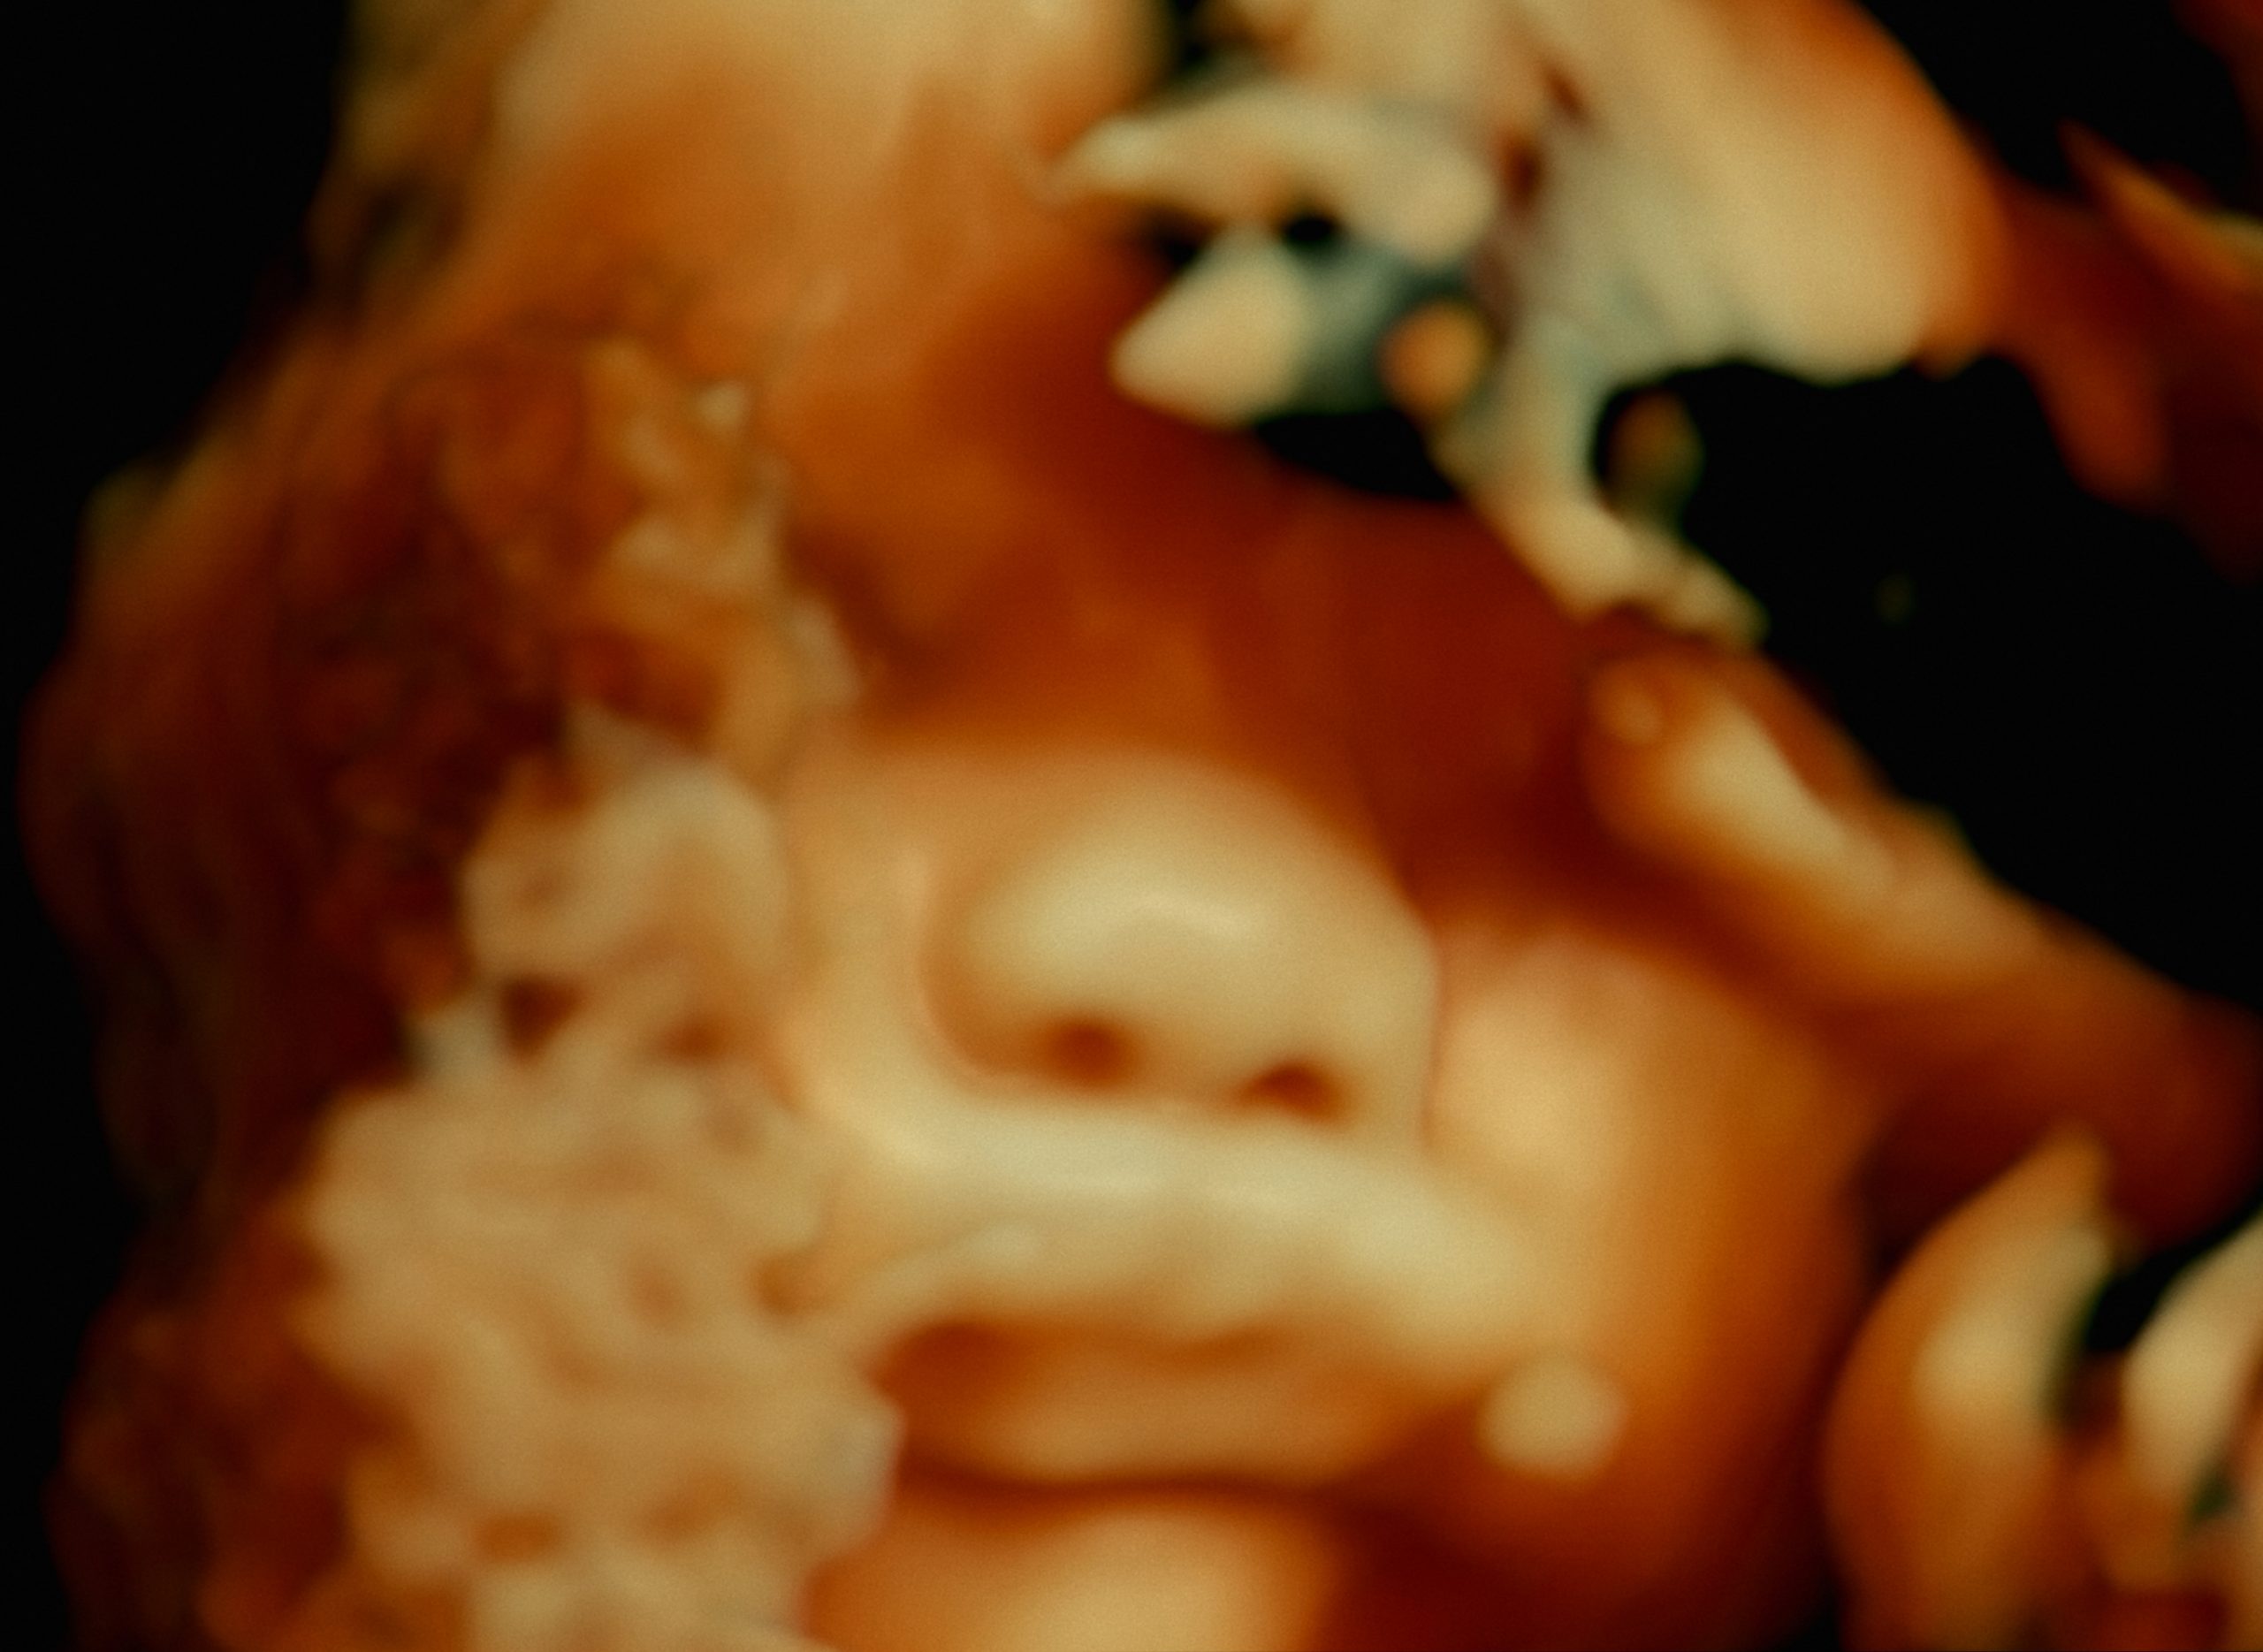

De Humani Corporis Fabrica escorts us on a whirlwind tour of various Parisian hospitals and specialist units as seen through the shallow-focus eye of a tricked-out endoscopy camera. Once through the doors of each institution, we then burrow deeper, into the cloistered privacy of operating theatres and, occasionally, inside the damaged bodies of the patients themselves.

To those who might be put off by the prospect of monitoring a diverse array of surgical procedures in extreme close-quarters, fear not: there’s nothing here that’s intended to provoke or repel, and the filmmakers can never be accused of exploiting their images as example of morally-detached gore. Quite the opposite in fact, as we are shown: the hard (but necessary) realities of, say, an emergency cesarean section; the jaw-dropping array of instruments and techniques used in a keyhole prostate examination; and the resilience of a damaged spinal column as it takes a pummelling from mallets, drills and wrenches while having metal struts attached to it.